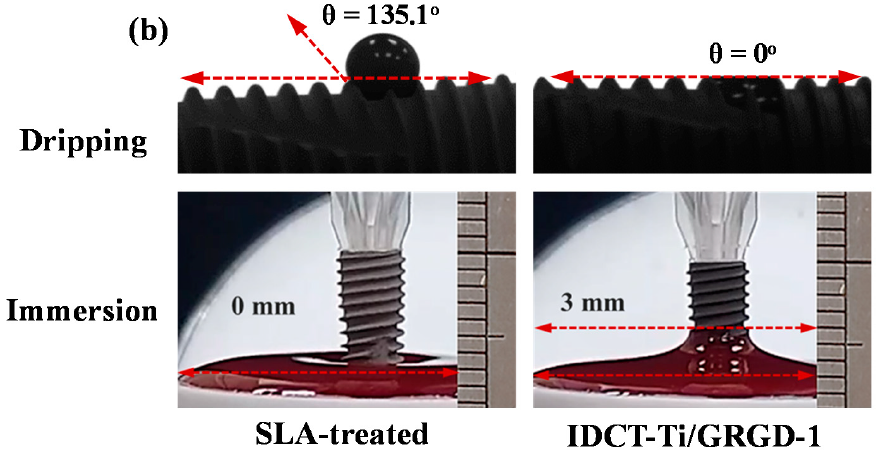

3.3. Wettability of the Investigated Implants

3.4. Hemocompatibility of the Investigated Implants